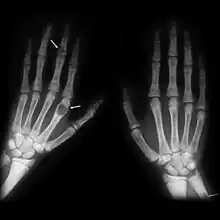

X-rays may also be used to diagnose the disease. Usually, these X-rays will show extremely thin bones, which are often bowed or fractured. However, such symptoms are also associated with other bone diseases, such as osteopenia or osteoporosis.[29] Generally, the first bones to show symptoms via X-ray are the fingers.[22] Furthermore, brown tumors, especially when manifested on facial bones, can be misdiagnosed as cancerous.[29] Radiographs distinctly show bone resorption and X-rays of the skull may depict an image often described as "ground glass" or "salt and pepper".[30][31] Dental X-rays may also be abnormal.[2]

Cysts may be lined by osteoclasts and sometimes blood pigments, which lend to the notion of "brown tumors." Such cysts can be identified with nuclear imaging combined with specific tracers, such as sestamibi.[3] Identification of muscular degeneration or lack of reflex can occur through clinical testing of deep tendon reflexes, or via photomotogram (an achilles tendon reflex test).[24][32]

The brown tumors commonly associated with OFC display many of the same characteristics of osteoclasts.[23] These cells are characteristically benign, feature a dense, granular cytoplasm, and a nucleus that tends to be ovular in shape, enclosing comparatively fine chromatin. Nucleoli also tend to be smaller than average.[18]